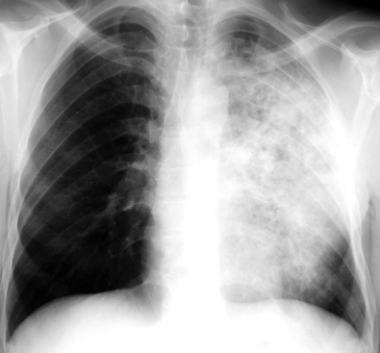

Describe the RA of tuberculosis with lobar consolidation

dense well-defined consolidations usually apical

(image shows consolidation in upper and lower lobes)